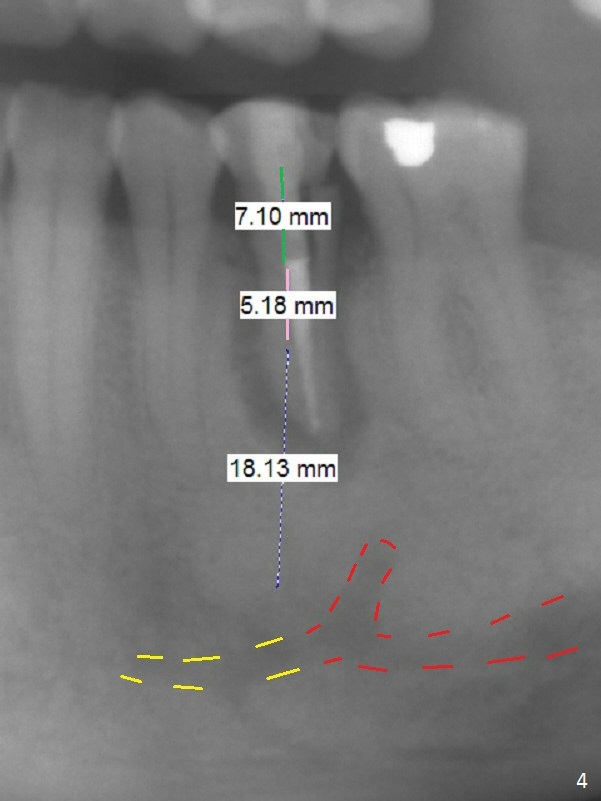

A 53-year-old man (probably bruxer, long roots) has 3 missing teeth (Fig.1 #14,18,29) and 1 fractured tooth (Fig.2 #20).  The fractue is associated with deep buccal pockets.  The buccal plate is most likely defective.  After extraction (Metronidazole), start osteotomy lingual and mesial (Fig.3 red long arrow) to reduce damage to the Mental Loop (Fig.4 red dashed line).  Damage to the Incisive Canal (yellow dashed line, the continuum of the Inferior Alveolar Canal after giving off the Mental Loop) is less significant.  Since the defect is long, use the longest implant and place it deep.  A long abutment (7 mm, green) with 5 mm cuff (pink) is required.  To have sufficient buccal gap for bone graft and probably membrane, the smallest two-piece implant is necessary (3.8 mm).